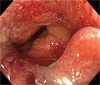

Case presentation: A 71-year-old woman presented to our hospital with bloody stools. A colonoscopy revealed type 2 advanced cancer in the rectum, and a histological examination exposed a well-differentiated adenocarcinoma. Abdominal enhanced computed tomography divulged rectal wall thickening without significant swelling of the lymph nodes or distant metastasis. Pelvic magnetic resonance imaging showed tumor invasion beyond the intrinsic rectal muscle layer. The patient was diagnosed with cStage IIa (cT3N0M0) rectal cancer and underwent low anterior resection using the hinotori™ Surgical Robot System. Based on an adequate simulation, surgery was safely performed with appropriate port placement and arm base-angle adjustment. The operating time was 262 min, with a cockpit time of 134 min. Subsequently, the patient was discharged 10 days postoperatively without complications. The pathological diagnosis was pStage IIA (cT3N0M0) and the circumferential resection margin was 6 mm.